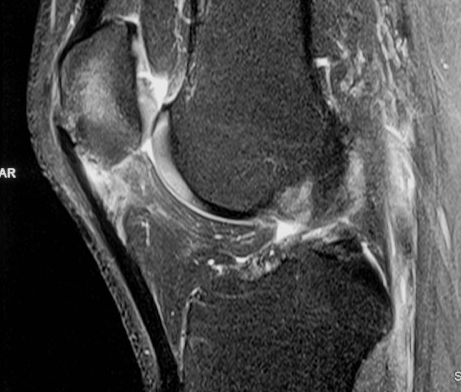

MRI

Cyst / Degeneration

Traction spurs / calcification / ossicles